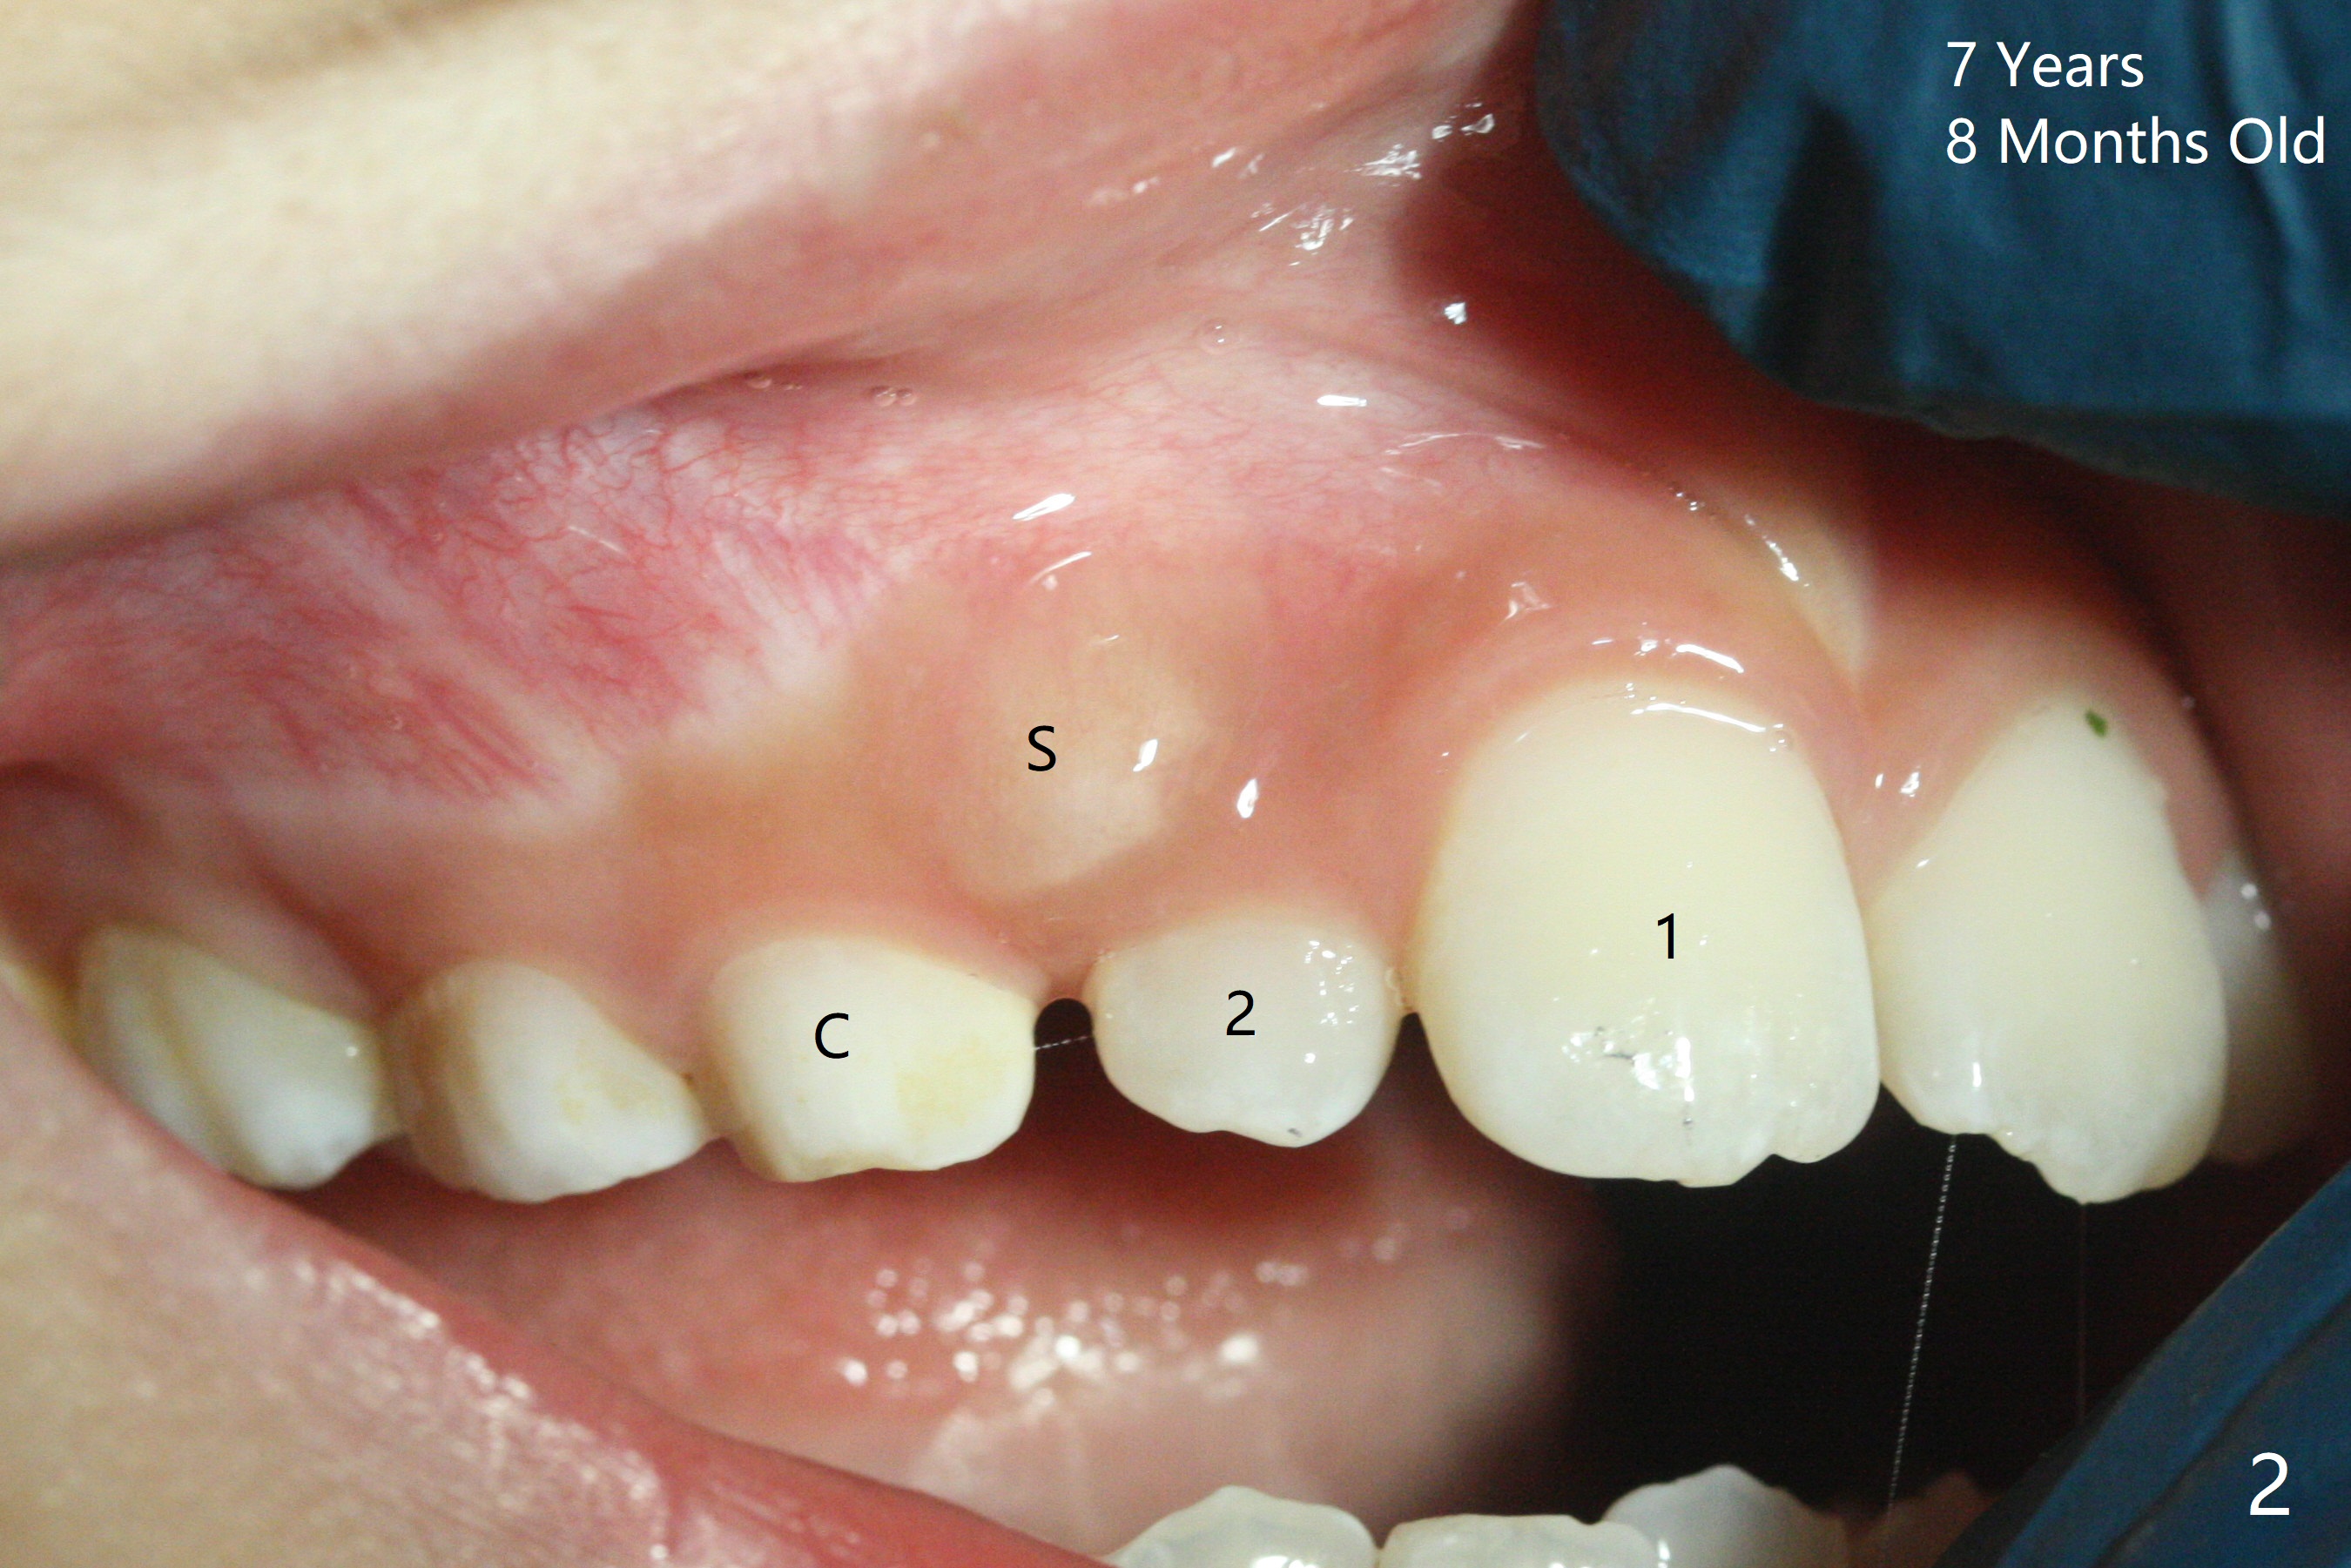

A 6-year-old woman presents to office for limited exam for caries (Fig.1). What was neglected is a super-numerary tooth (S) between UR2 and 3. One year later, the extra tooth appears to be erupting (Fig.2) and linguali-zing UR2 (Fig.3 arrow). PA shows that the extra tooth looks like a lateral (Fig.4). CT will be taken to decide which tooth needs for extrac-tion. The super-numerary tooth (S) blocks UR3 descent, as compared to that of UL3 (Fig.5). The super-numerary tooth with an abnormal cingulum (Fig.6 *) and dens in dente (Fig.6 ^) should be extracted.